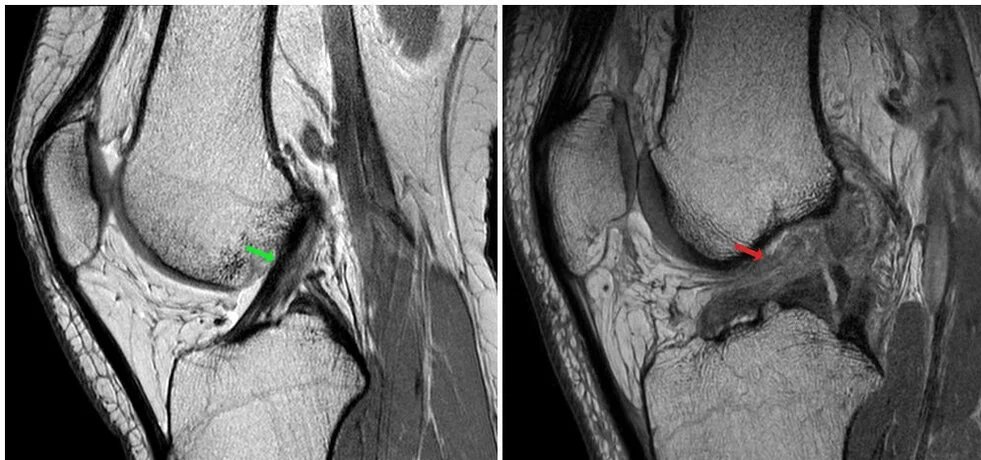

- اختبارات تصويرية: التصوير بالرنين المغناطيسي (MRI) هو الأداة الأساسية لتأكيد قطع الرباط ورصد أي إصابات مصاحبة مثل تمزق الغضروف.